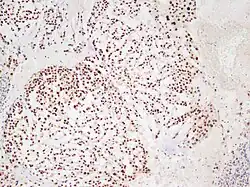

In 2015 the first consensus guidelines for the diagnosis and treatment of chordoma were published in The Lancet Oncology.[13] These tumors express brachyury and cytokeratin, which can be detected by immunohistochemistry.

Chordoma showing nuclear staining for brachyury using immunohistochemistry.

There are three histological variants of chordoma: conventional,[14] chondroid and dedifferentiated.

• The histological appearance of classical chordoma is of a lobulated tumor composed of groups of cells separated by fibrous septa. The cells have small round nuclei and abundant vacuolated cytoplasm, sometimes described as "physaliferous" because of their cytoplasmic vacuoles, and their resemblance to the physalis plant.